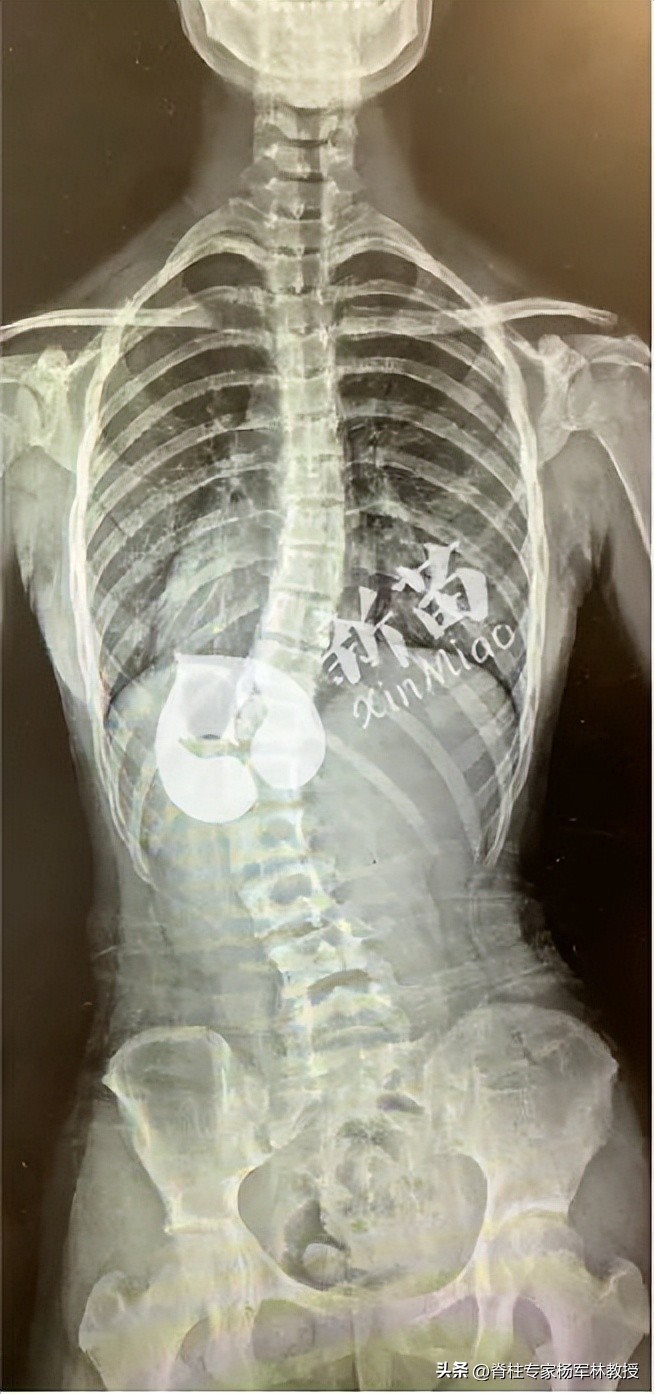

脊柱侧弯是指背部的脊柱向一侧或双侧偏移躯干的中轴线,形成“C”型或“S”型弯曲。国际脊柱侧凸研究学会(Scoliosis Research Society)规定:如果站立位脊柱正位X光片上的弯曲角度(cobb角)大于10°时称为脊柱侧弯,亦称为脊柱侧凸。

从背面的X片来看,脊柱有弯曲畸形,常发生在胸椎段和腰椎段。

脊柱侧弯后胸椎受累,导致整个肋与肩部向一侧倾斜,整个胸廓向一侧倾斜,接着就造成了高低肩。